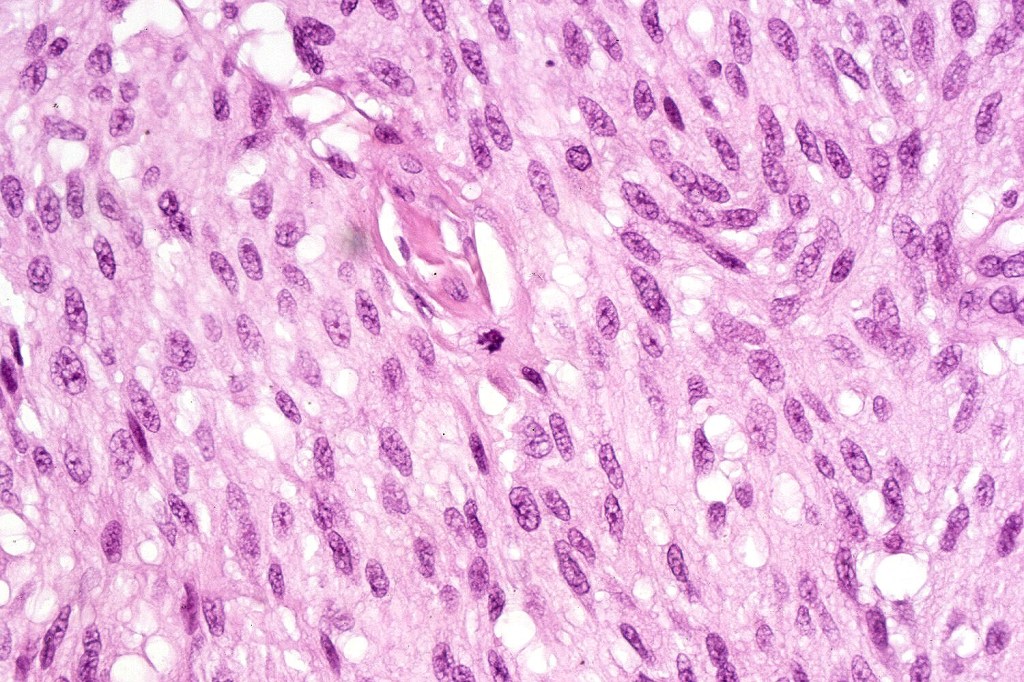

•Matures with depth-often best recognized at scanning/low power magnification & readily confirmed with S100 or MART1

•Maturation implies nest size and cell size diminishing with depth, at the base, the infiltrate may have a single cell infiltrating pattern

•Mitoses can brisk in younger patients and should not be taken as indicating melanoma

•Mitoses are restricted to the superficial aspect on the nevus and are never atypical